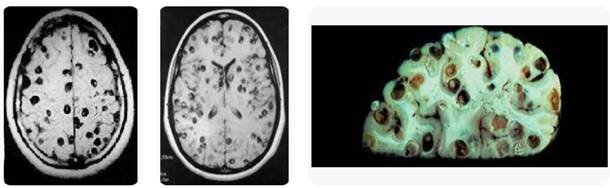

Hình 1. Ấu trùng sán dây lợn ở thần kinh trung ương | Nguồn: CDC, 2021

Hình 2. Nang sán trong nhu mô não và hình ảnh trong nhu mô não khi mổ |Nguồn: Radiologie, 2016

Hình 3. Nang ấu trùng sán dây lợn trong nhu mô não bệnh nhân